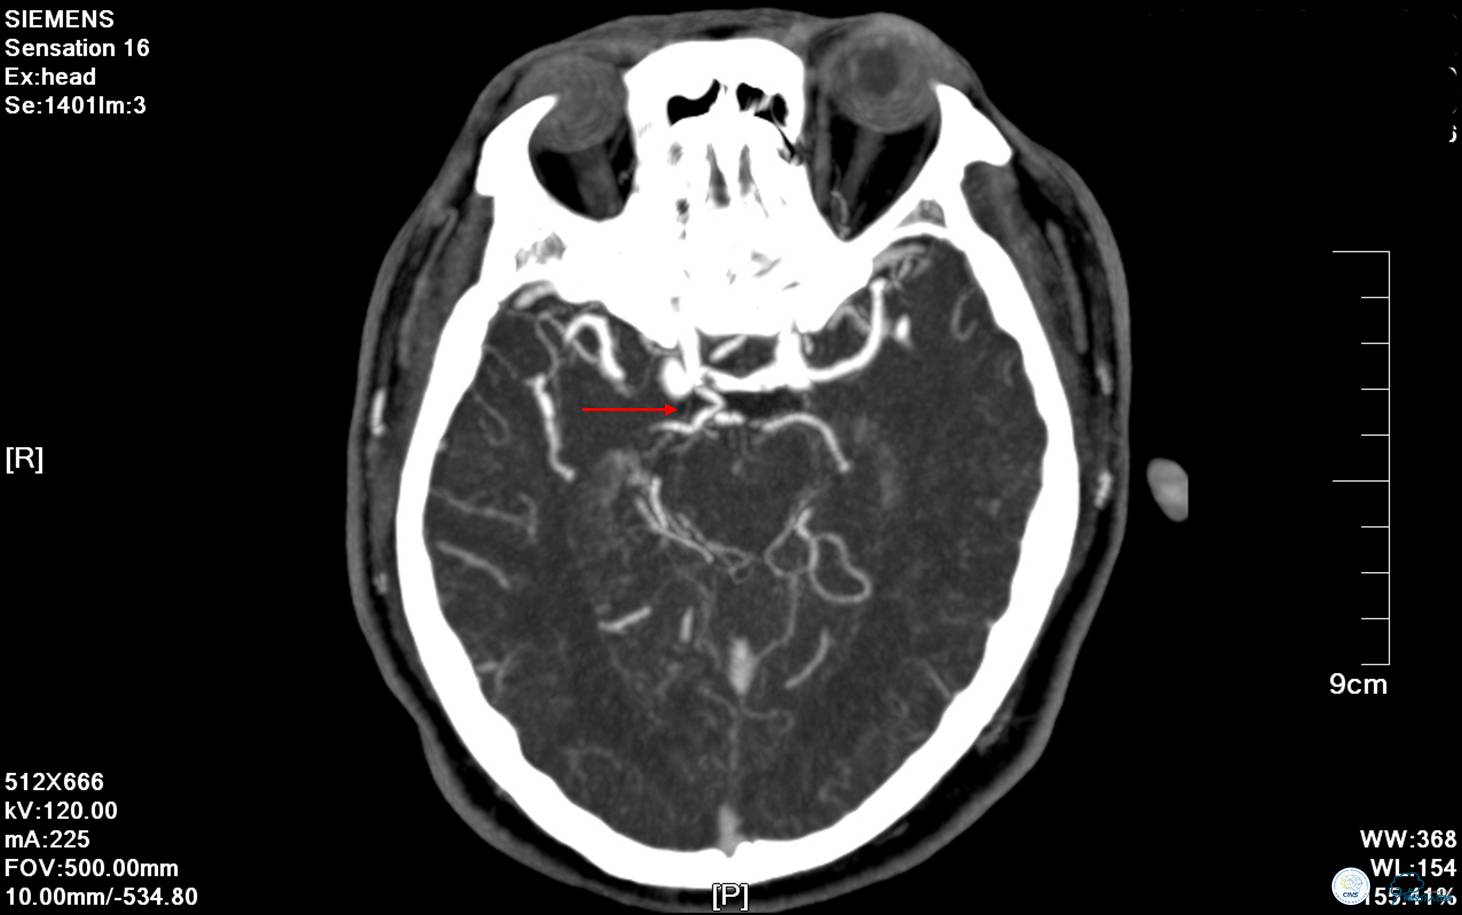

▼ CTA提示基底动脉中段闭塞。

▼ CTA:右侧后交通动脉开放、左侧大脑后P2段闭塞。